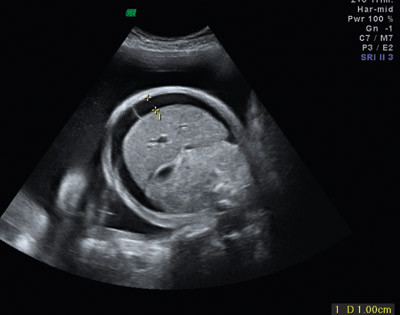

Figur 1  Ultralydbilde, tverrsnitt av føtal abdomen som viser ascites ved hydrops foetalis

En kvinne kan bli immunisert mot blodtypeantigener som hun selv mangler, og som fosteret har arvet fra far. Immuniseringen kan gi hemolyse av barnets erytrocytter (hemolytisk sykdom hos foster og nyfødt). Hemolysen kan føre til at barnet utvikler anemi, som kan føre til hydrops foetalis, som ubehandlet kan ha fatalt forløp (fig1). Før fødselen vil bilirubinet som frigjøres ved hemolysen, passere placenta og bli konjugert og utskilt av mor, men hos den nyfødte vil ukonjugert bilirubin akkumuleres fordi leveren ikke har tilstrekkelig konjugeringskapasitet. Ukonjugert bilirubin kan trenge inn i basalgangliene og gi varige nevrologiske skader.